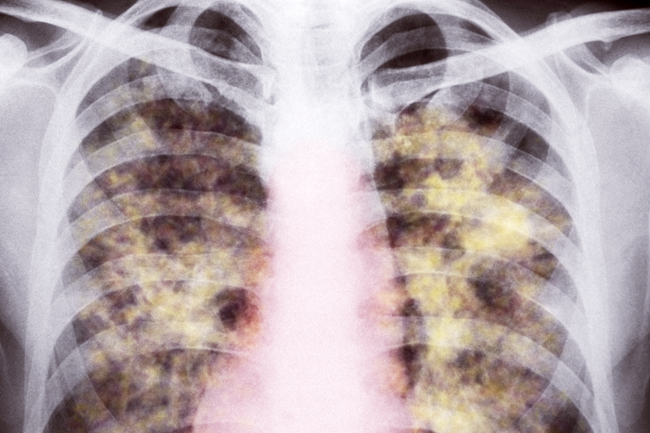

Half a million – that’s the number of backlogged health claims from mineworkers with lung diseases that South Africa plans to unblock with a ZAR1.5 billion fund.

The goal is to compensate current and ex-mineworkers who have submitted valid claims but haven’t received payouts for health issues resulting from TB, silicosis and other illnesses. The Department of Health and Chamber of Mines, along with eight mining companies such as AngloGold Ashanti, African Rainbow Minerals, Gold Fields and Sibanye Gold, hope that Project Ku-Riha (meaning ‘compensation’ in Tsonga) will streamline these claims.

Two one-stop diagnosis and service centres were unveiled in Carletonville and Mthatha. The money will come from a ZAR2.9 billion fund administered by the Medical Bureau for Occupational Diseases.

Miners from neighbouring countries who worked in South Africa can also apply.